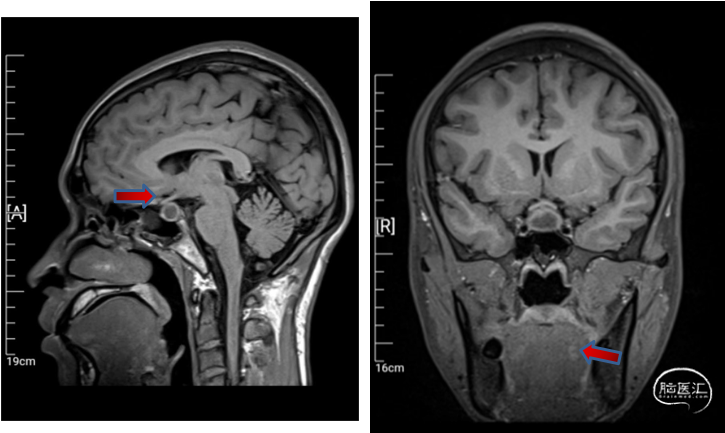

垂体MRI平扫+增强:

垂体前叶异常信号灶伴垂体柄增粗、强化,鞍內占位,Rathke囊肿?炎性病变?

垂体后叶高信号未显示